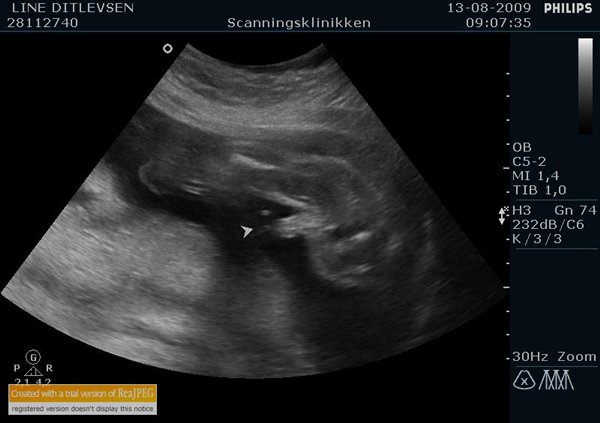

Hvis man vil være mere sikker, så bestil en 3D-scanning, der kan de meget meget bedre se det

Da vi har til kønscaning tog de hende 3 timer inden hun kunne sige hvad det var. Altså hvor vi var ude og gå lidt også komme tilbage også ude og gå igen osv. Men når man så hører scanings cd bliver man virkelig i tvilv, da hun i det en øjeblik siger at den ikke vil vise sig og næste øjeblik at det er en drenge også igen den ikke vil vise sig også igen drenge også tilbage igen til at den godt nok ikke vil vise sig.